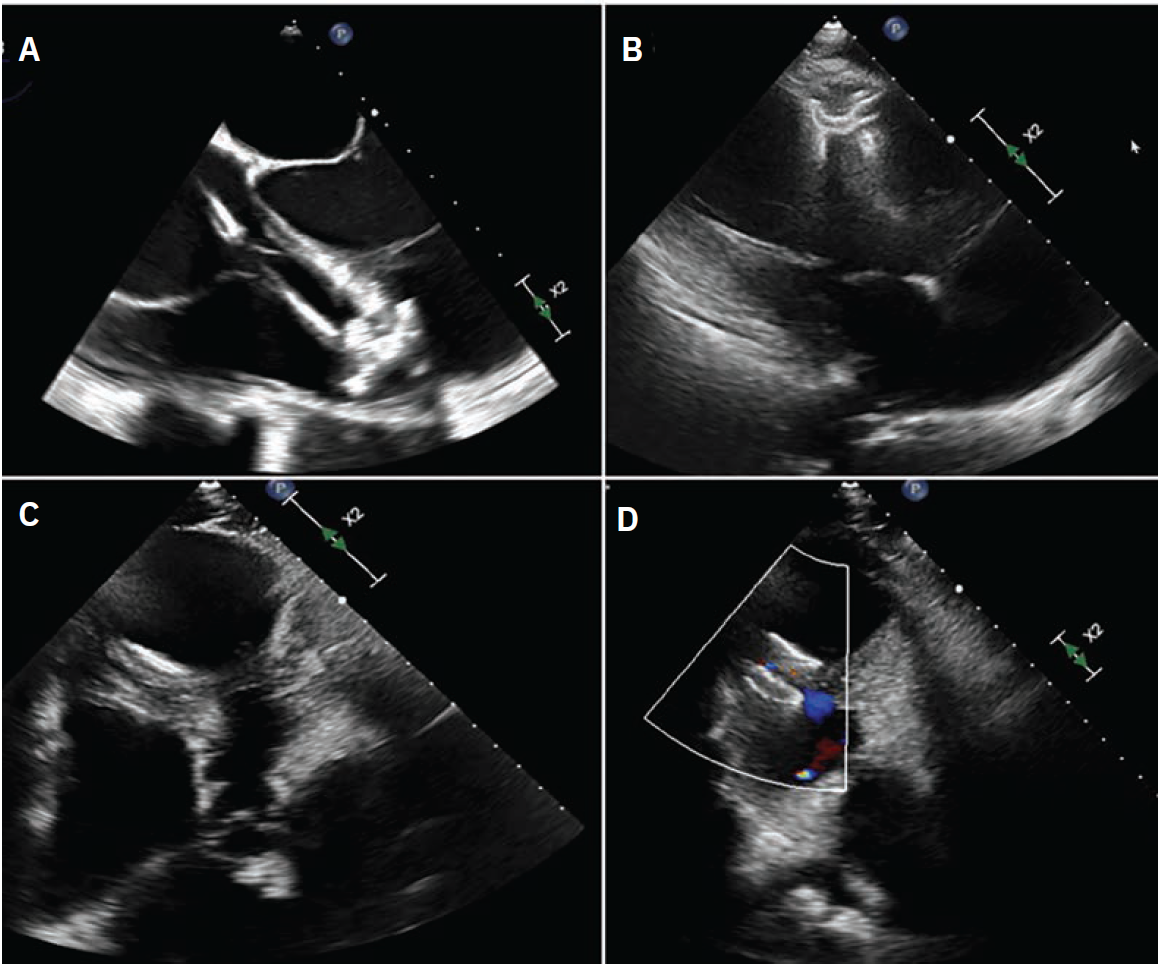

In October 2024, he presented with a one-month history of progressive dyspnea on exertion (DOE) and orthostatic dizziness. He denied chest pain. On examination, there was a loud, harsh, holosystolic murmur at left sternal border. Initial EKG showed Q waves with <2 mm ST elevations in leads V1-V3 and diffuse T wave inversions in the precordial leads, I and aVL (Supplementary Figure 2). Initial clinical diagnosis of delayed presentation of anterior STEMI with left ventricular (LV) aneurysm and VSD was confirmed with TTE which showed LV ejection fraction 20-25%, apical dyskinesis, and VSD with left-to-right flow on color Doppler (Figure 1, Video 1 [at end of case section]).

Transthoracic and transesophageal echocardiography showing severely reduced LV function and VSD.

LV = left ventricular; VSD = ventricular septal defect.